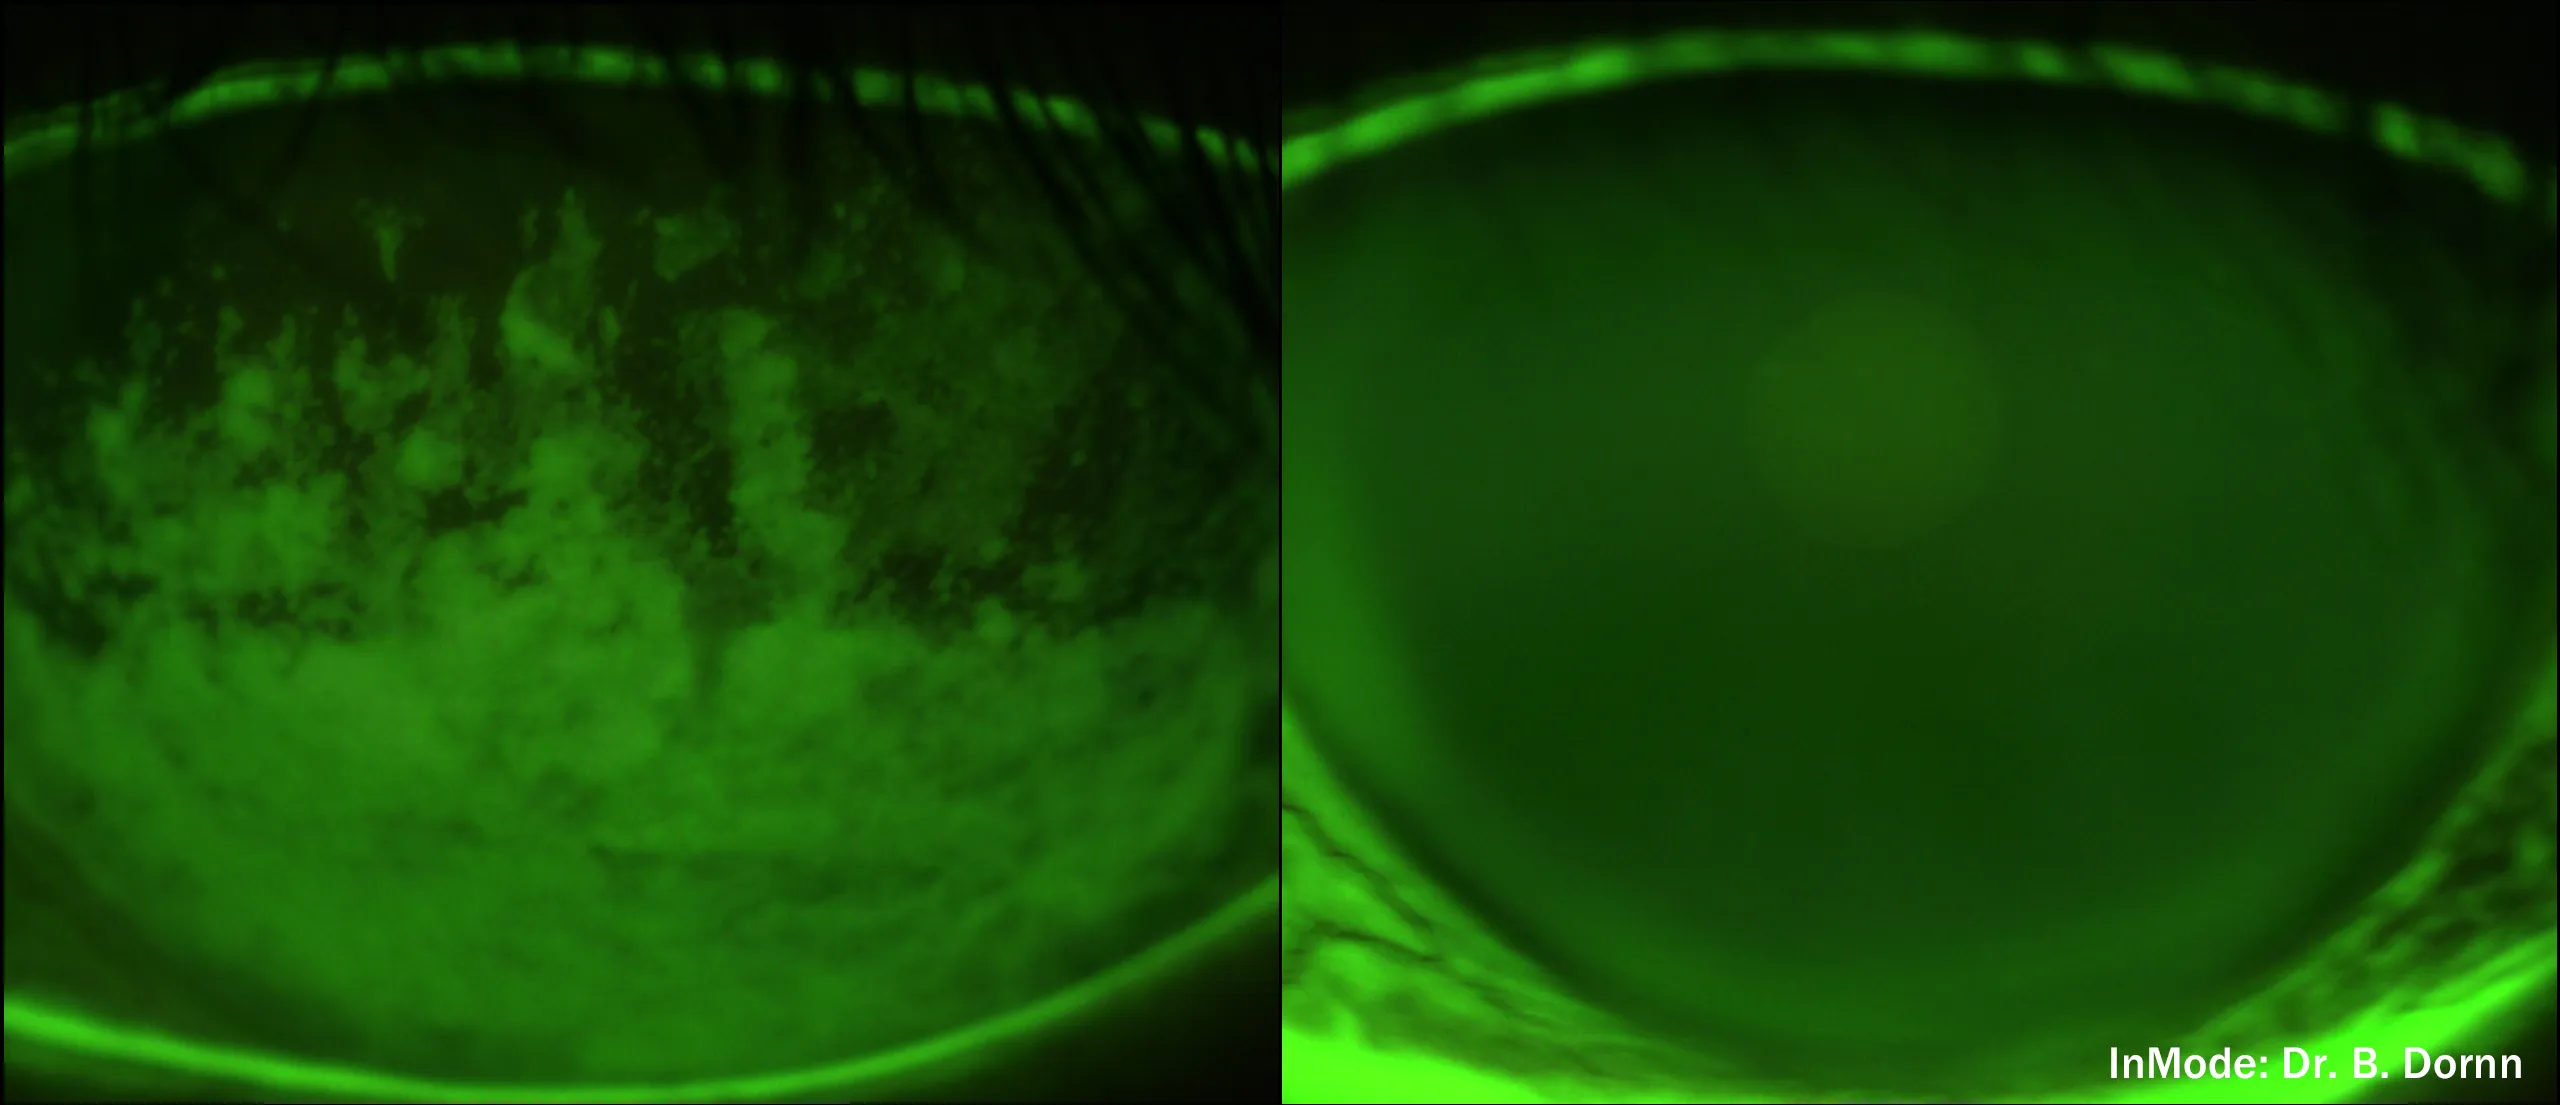

INMODE Lumecca Intense Pulse Light treatment (IPL) works to control the inflammatory process and to stop the vicious cycle of inflammation and to reduce the need for medications. IPL treats ocular rosacea, Meibomian Gland Dysfunction, and Inflammatory dry eye. It has been shown to decrease demodex and bacteria around the eyelids. The powerful bursts of light also close off blood vessels that release inflammation in ocular rosacea.